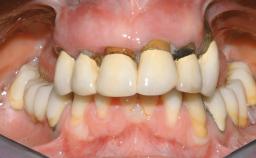

Immediate Loading of Eight Implants in the Maxilla and Six Implants in the Mandible and Final Restoration with Three-Unit and Four-Unit FDPs

Extensive scientific evidence has confirmed that immediately loaded implants with fixed full-arch provisional restorations can osseointegrate with success rates similar to conventionally or delayed loaded implants. A number of immediate-provisionalization techniques for edentulous jaws have been described. Some protocols differ when it comes to prefabricated provisional templates versus complete denture conversion; intrasurgical impressions versus direct relining; and cemented versus screw-retained provisional restorations. In this context, complete-denture conversion has been proposed for either intrasurgical impressions or direct relining. Another possibility is the utilization of a prefabricated provisional to be adapted either in the mouth (by direct relining) or in the laboratory (on a working model obtained from an intrasurgical impression).